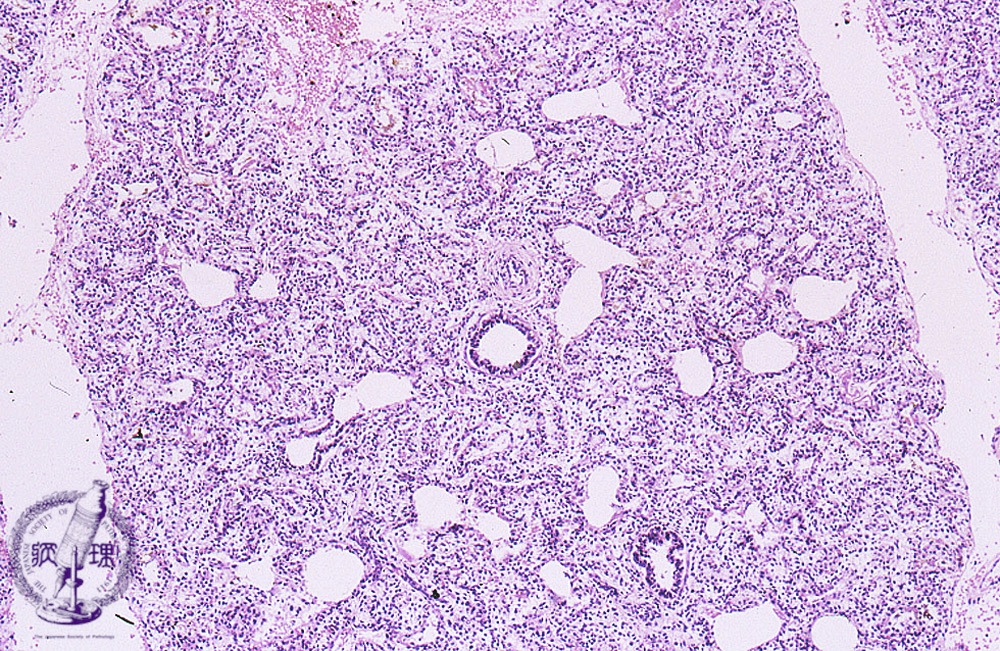

Microscopic view (HE stain, low power view): Appearance of atelectasis in a stillborn infantfs whose lungs never expanded.

Click the image to see the enlarged image.

• There is no guidance by arrows.